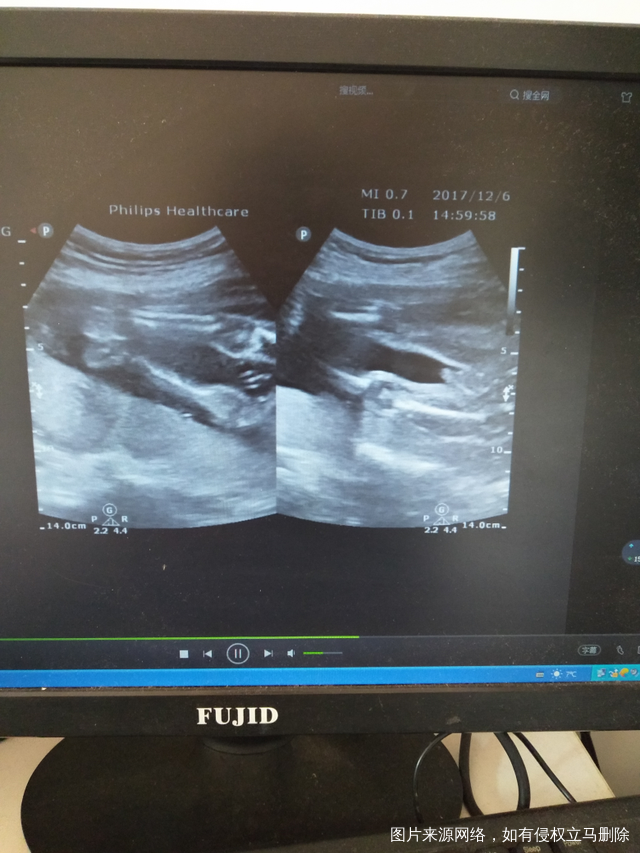

有宝宝的性器官图片 只是我还看不懂?有经验的宝妈可以帮我看一下

吗?